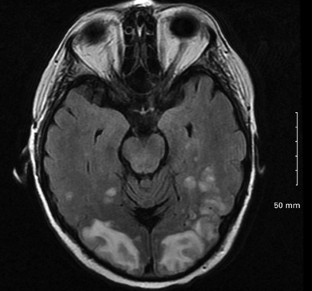

Sukumaran, S., George, B., Nair, H. et al. Posterior reversible encephalopathy syndrome as a consequence of high dose steroid administration after autologous PBSCT. Bone Marrow Transplant 45, 779–780 (2010). https://doi.org/10.1038/bmt.2009.211